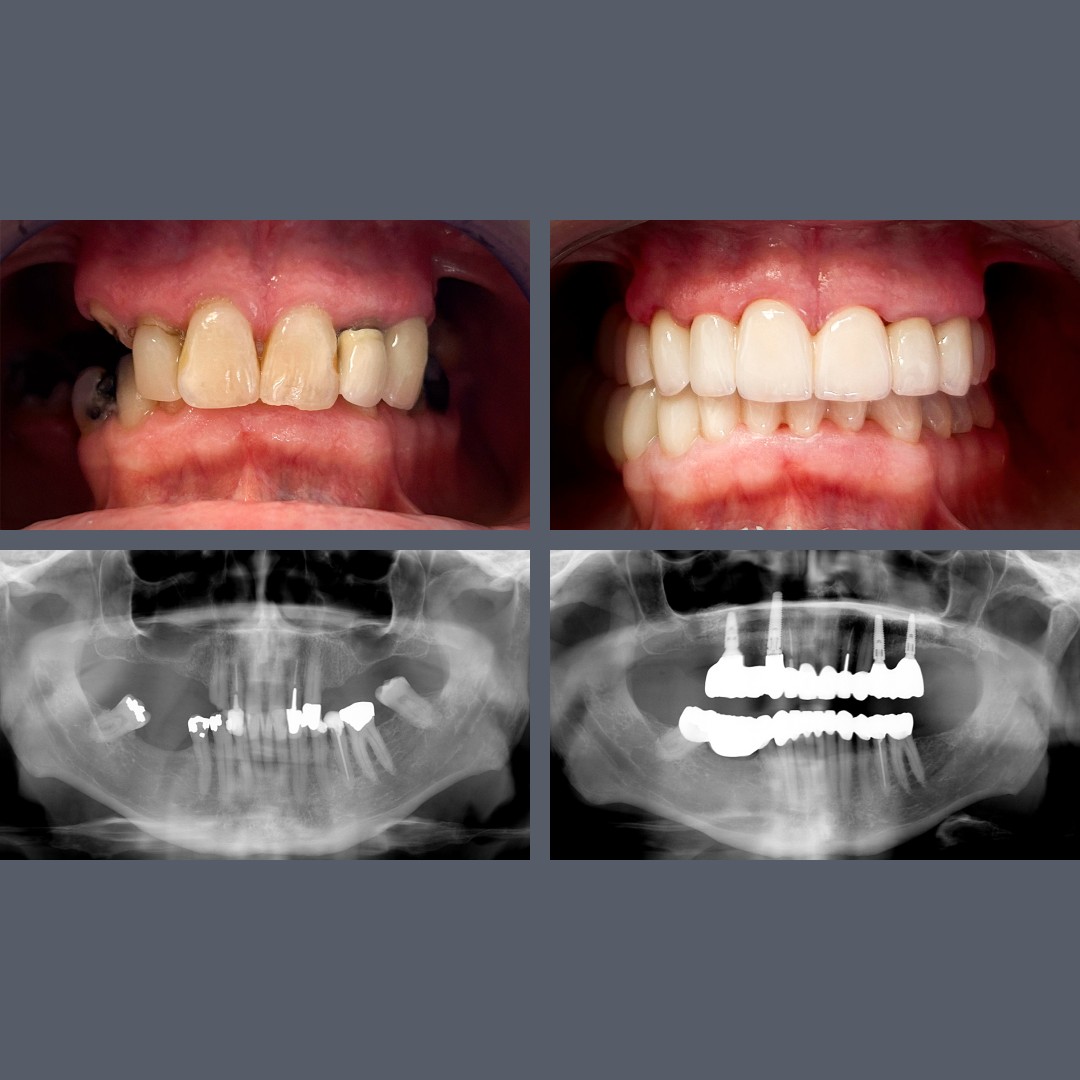

Severe Gum Disease and Tooth Loss – All-on-4®: Fixed Full-Arch Prosthesis in 48 Hours

Treatment: ALL-ON-4®